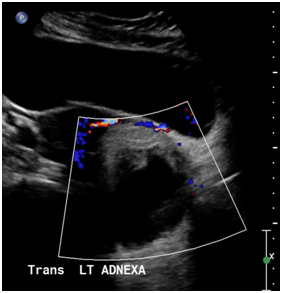

This 29-year-old, Para 1-0-0-1 female with a history of asthma and obesity presented to the emergency department complaining of severe left lower quadrant pain and vomiting. Her initial CT Abdomen/Pelvis scan showed a 10 cm complex mass in the left adnexa, likely a Mature Cystic Teratoma (MCT), and an incidental 4.2 cm adrenal mass. Endocrine investigation of the adrenal mass was benign; findings were consistent with lipogenic adenoma. Pelvic sonogram showed a left adnexal mass (8.8 cm) (Figure 1) and a pelvic MRI confirmed an 8 cm dermoid cyst (MCT). One year prior to the study the patient had no adnexal masses as concluded by review of an obstetrical sonogram. On pre-operative evaluation, the patient’s CA 19-9 was 2179.62 U/ml. Other tumor markers, including HE4 (25 U/ml), CEA (<0.5 U/mL), CA125 (8.7 U/mL), and AFP (7.1), were all within normal limits. Intraoperatively a large dermoid cyst was found torsed and adhesed to the posterior uterine wall, right adnexa and bowel. Detorsion, lysis of adhesions and left salpingo-oophorectomy were performed. The resected specimen consisted of multiple fragments of reddish/tan, soft tissue and material with hair, measuring 8 x 6 x 6cm in aggregate. The final pathological report demonstrated: mature cystic teratoma (dermoid cyst). Postoperatively, repeat CA 19-9 measurement dropped to 270.30 U/mL and eventually down to 33.98 U/mL.